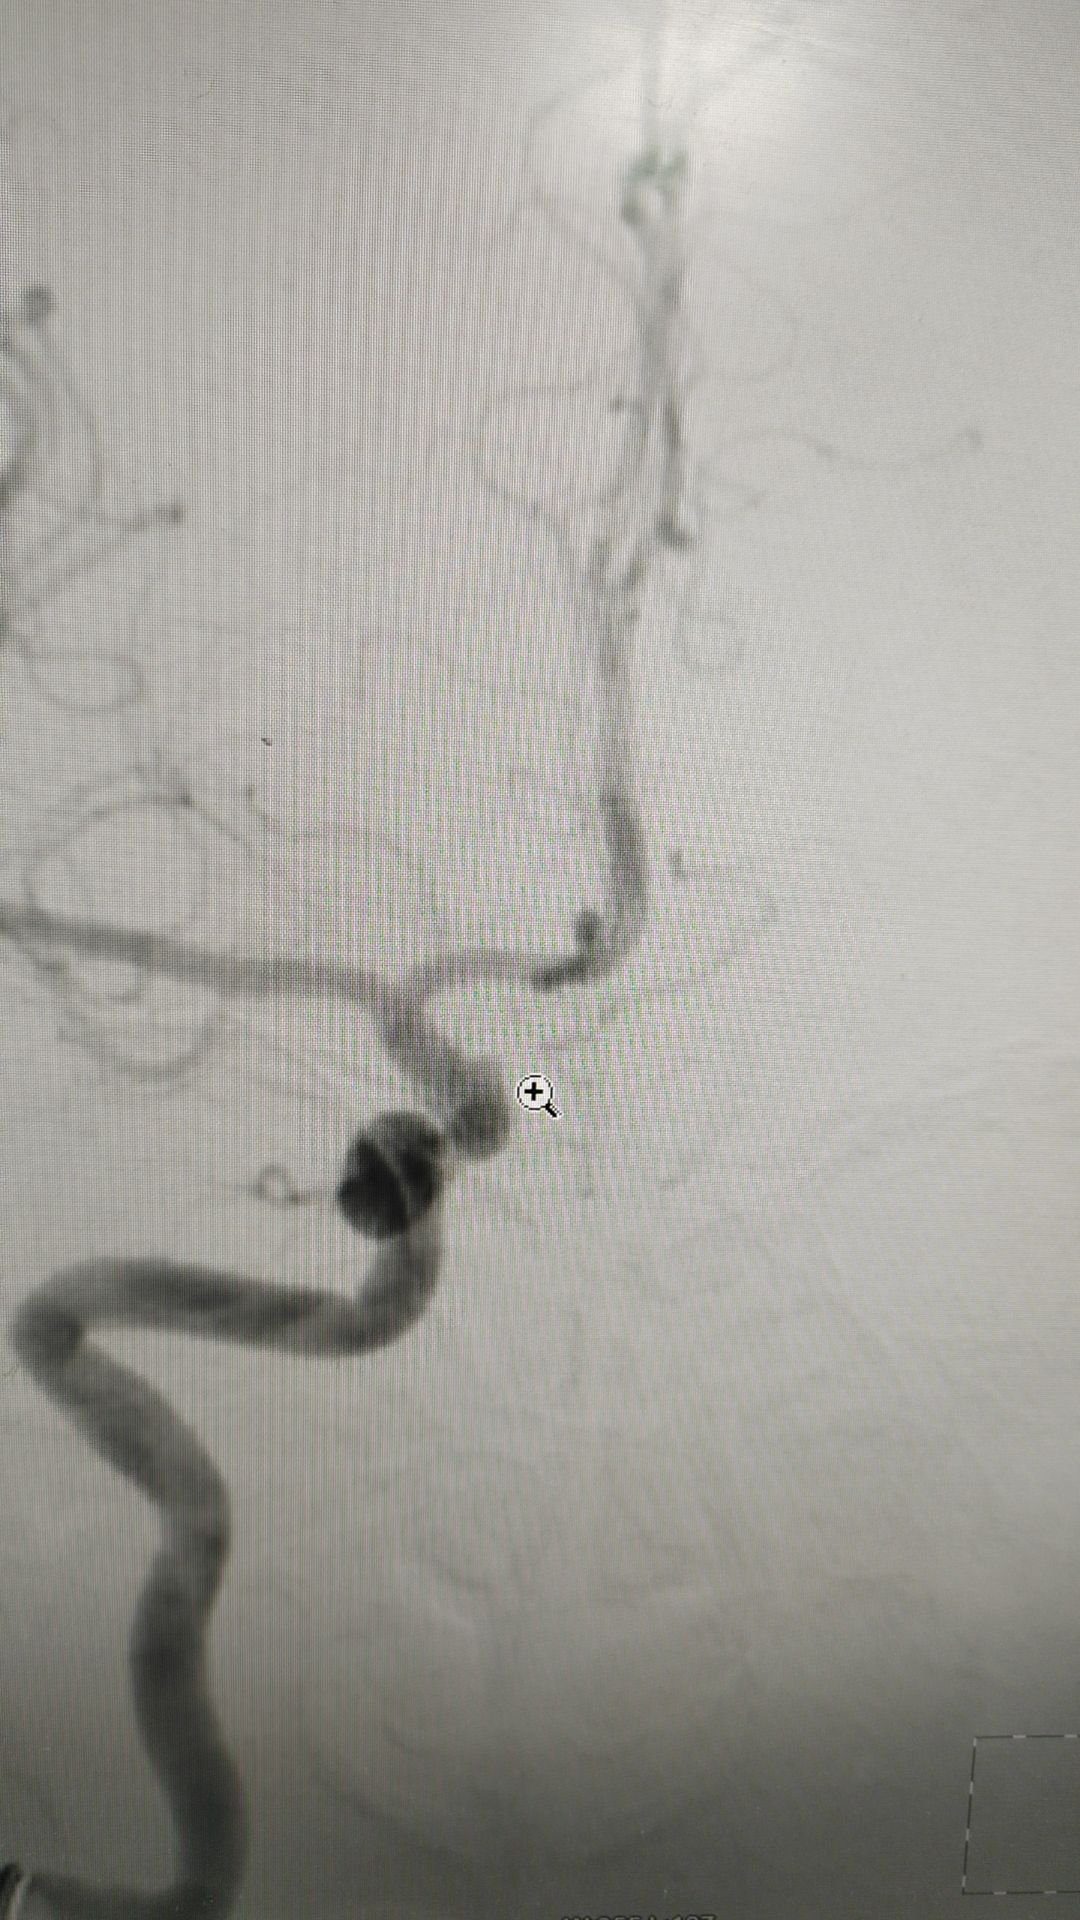

第三次出血后急诊上台,造影显示动脉瘤增大

工作位造影,瘤体约6.1*5.5mm,更加确认是血泡样动脉瘤!

Lvis支架半释放后准备处理瘤颈,手头上没有3.5*15的支架了,选择3.5*20,颈内动脉虹吸弯处担心双支架可能打开不良,拟单支架辅助,所以瘤颈处理很关键,最好能出来铆钉效果!

瘤颈处理满意,按摩支架!

术后工作位造影

换个位置可以看见瘤颈填塞满意,铆钉效果出来了!